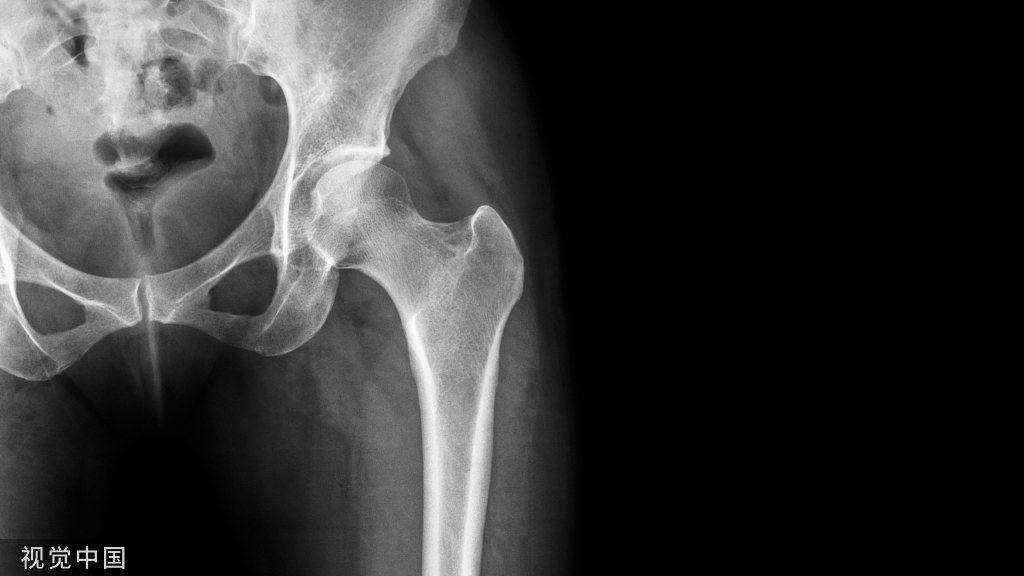

02

骨质疏松性骨折PVP